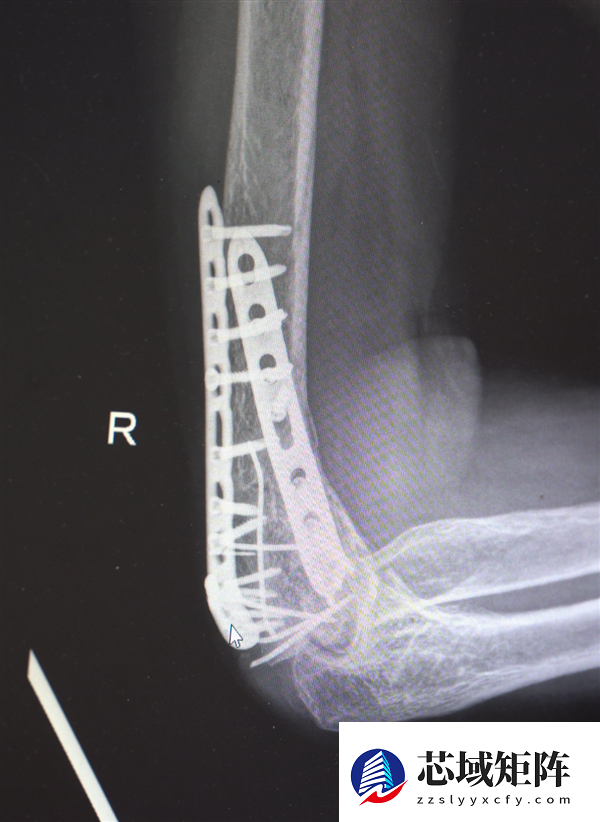

鉴于男子多处骨折,其中最严重的当属右肘部C3型粉碎性骨折,关节面及髁上严重粉碎(碎成了七块),肘关节易粘连,复位固定难度极高。

最终医疗团队采用了“拼古董”式复位固定技术,就像修复一件珍贵的古董瓷器,先拼接大块骨块再贴合小块,先后进行了两次手术。

部分手术后拍摄的影像